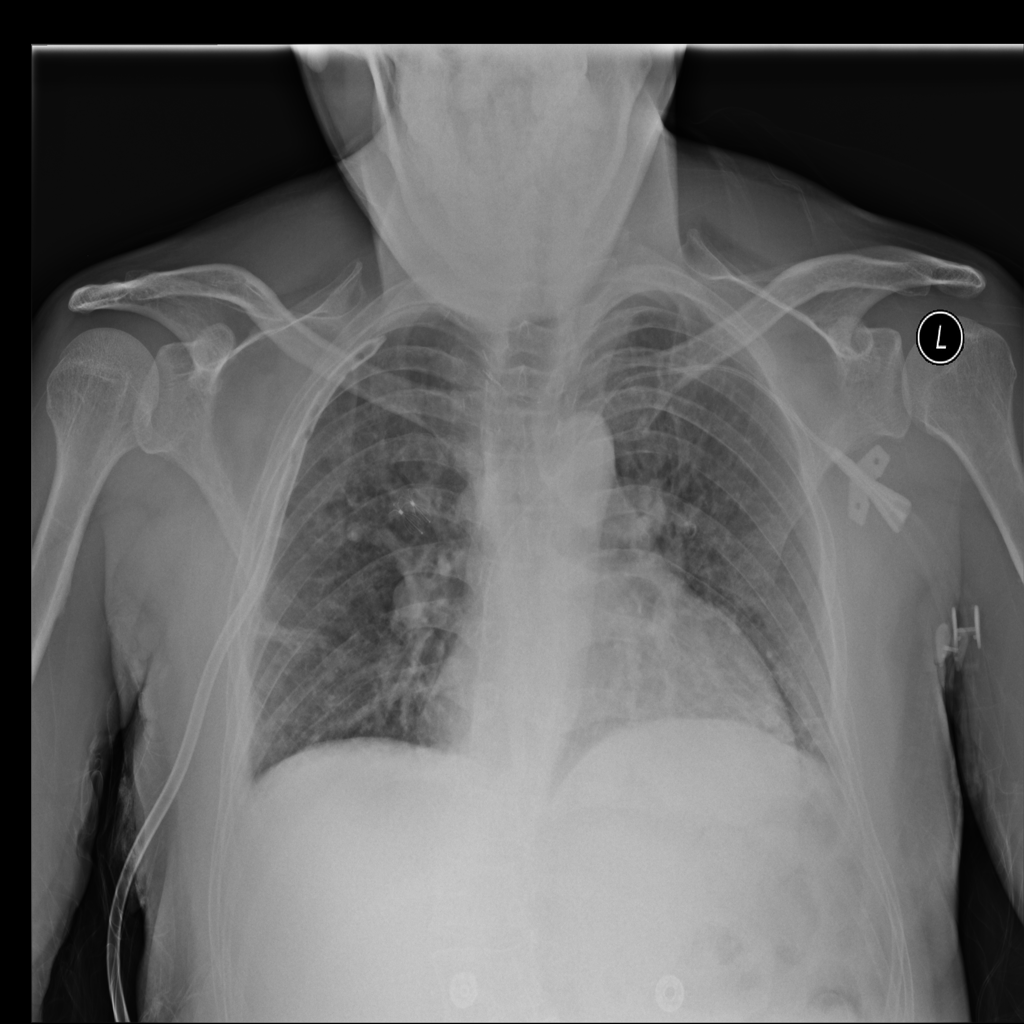

PAT-DB80 · IMG-001Atelectasis

PAT-DB80 · IMG-001

PA